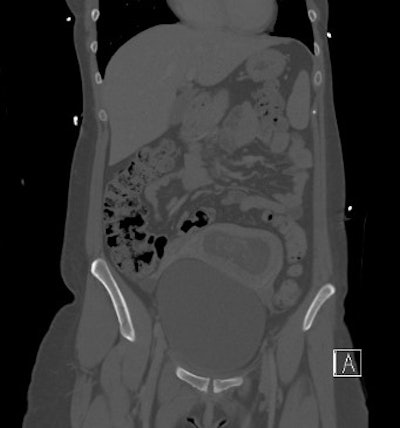

- 8 abdominopelvic CT exams

The number of CT exams of pregnant patients increased from three to four per year in 2008 to 2011 to 11 per year in 2012, a result that corresponding author Dr. Federica Zanca, also from University Hospitals Leuven, called "surprising" in an email to AuntMinnieEurope.com. In addition, three pregnancies were found by accident on abdominopelvic CT, which Zanca said was also surprising.

Abdominopelvic CT | 28.7 (range: 6.7-60.5) |

The radiation dose for all but the abdominopelvic CT exams were considered negligible, according to the researchers.